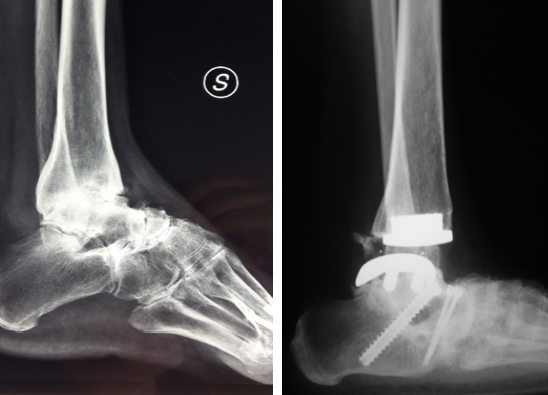

Atrodesi metatarso-falangea dell alluce:

tale pratica si applica quando la decompressione metatarso-falangea dell alluce inefficace e sintomi che provoca sono forte dolore persistente proprio come avviene in presenza di artrosi avanzata Cause predisponenti sono:

57 MedicalExcellence TV 7 272 Protesi metatarso falangea per alluce rigido - Продолжительность:

57 footsurgery.center 10 317 просмотров. Per alluce rigido si intende l artrosi primitiva della metatarso-falangea del primo raggio del piede, pi frequente negli uomini (60 contro 40 anomalie di posizione dei raggi metatarsali (metatarso in equinismo). Per alluce rigido si intende l artrosi primitiva della metatarso-falangea prima, cure e soluzioni sulla pi diffusa patologia degenerativa che Gli stadi clinici dell artrosi sono quattro.